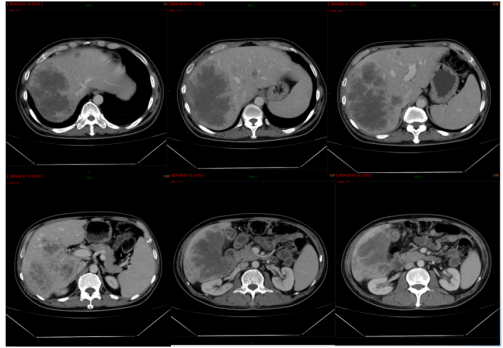

影像学检查:2024年7月30日,院外腹部CT显示乙状结肠管壁增厚,考虑肿瘤性病变(cT3N2,图1),2024年8月5日,肝脏MRI显示肝脏多发转移灶(侵犯门静脉右支、肝右静脉,图2)。2024年8月2日胸部CT显示双肺结节待排(图3)。

图2. 肝脏MRI